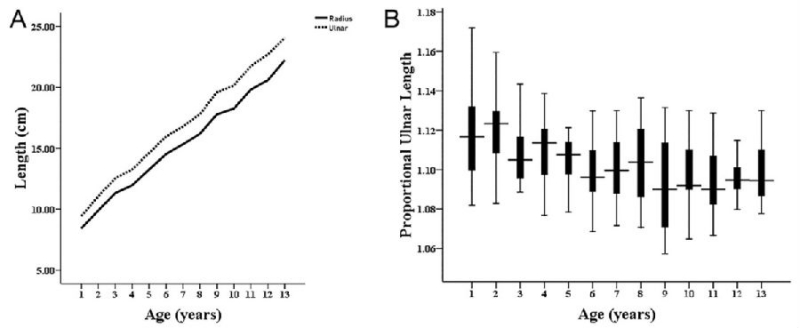

国内学者Huang等发现1-13岁健康儿童尺桡骨长度比值恒定在1.1左右。以此为标准治疗的30名患儿中,桡骨头复位及前臂功能恢复良好者高达93%(图6)。此外,不同医学中心对逐步尺骨延长的速度控制方案也有差异,包括0.75mm/d、1mm/d、0.25mm/6h等等,尚未有明确共识。

图6. 健康儿童尺桡骨长度比值